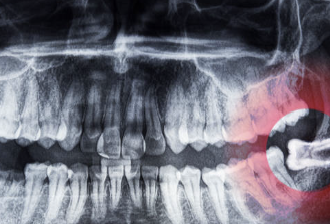

1. 치과에서 X-레이 검사를 통해 매복 사랑니의 위치와 상태를 확인합니다.